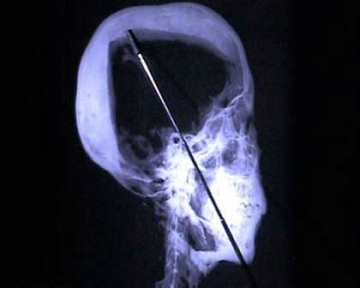

In der Grabkammer entdecken sie Farbspritzer an den Wänden - so als hätten die Maler unter enormen Zeitdruck gestanden.  Auch die Mumifizierung wurde nicht so sorgfältig durchgeführt, wie es für die Reise in die Ewigkeit normalerweise üblich war.  Der Leichnam des Königs war offensichtlich gleich eimerweise mit Harz übergossen worden.  Der Zustand der Mumie war schlecht - ist das ein Zeichen dafür, daß Spuren eines Verbrechens getilgt werden sollten, fragen sich die Fahnder.  Durch die Auswertung der Röntgenuntersuchungen von 1968 entdecken sie auch die mutmaßliche Todesursache.  Knochensplitter im Kopf des Herrschers deuten darauf hin, daß der Pharao erschlagen wurde.

Schädel des Tut-Ench-Amun

(Bildquelle: Spiegel-Online.de)

Der Schädel von Tut-ench-Amun